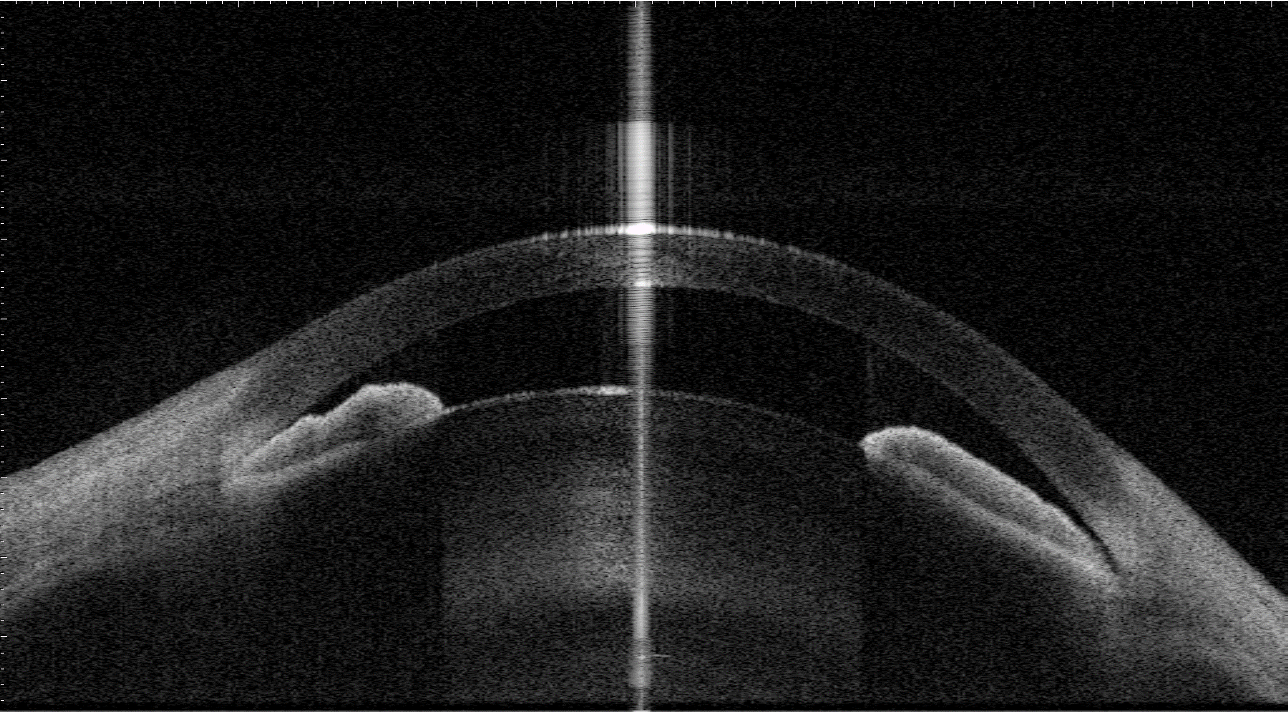

An eye with shallow anterior chamber and narrow angles captured by anterior-segment swept-source OCT. Image courtesy of Prof Clement Tham from Department of Ophthalmology and Visual Sciences, The Chinese University of Hong Kong.